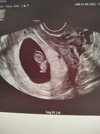

A oto mój boboludek😍

Załączniki

• 64e4ea4c-8c42-4190-b669-a347adf889d0.jpg

64e4ea4c-8c42-4190-b669-a347adf889d0.jpg

44,1 KB · Wyświetleń: 113